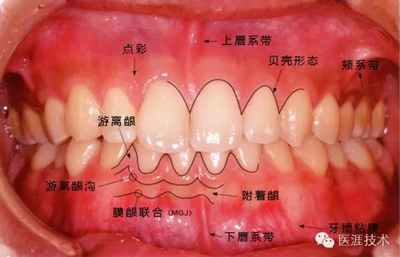

健康、正常的牙周組織如何形成?

健康牙周組織的牙齦邊緣呈珊瑚粉,邊緣牙齦略呈圓弧狀。牙間可見三角形的牙間乳頭,牙齦邊緣相連呈貝殼形。

附著齦與游離齦相連時,有時有游離齦溝存在(成人的30~40%)。

附著齦通過膠原纖維牢固結(jié)合骨骼與牙骨質(zhì),因此可見不可動、硬而緊繃的點彩(橘皮樣點狀凹凸)。

從牙齦牙槽粘膜到根尖有牙槽粘膜。牙槽粘膜為暗紅色,與骨骼結(jié)合較松,故可動。

健康且正常的牙周組織臨床圖像